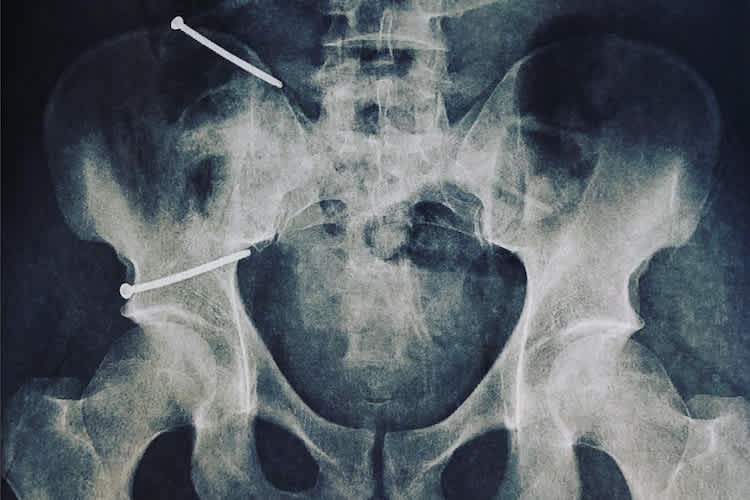

Obwohl der Kiefer-KTM-Pilot Glück im Unglück hatte und kein verschobener Bruch vorlag, legte er sich gleich am nächsten Tag unters Messer. Dies, um den Heilungsprozess zu beschleunigen, wie Aegerter vor dem Eingriff mitteilte. Dennoch war schon zu diesem Zeitpunkt klar, dass Aegerter den nächsten Grand Prix in Jerez (6. Mai) auf jeden Fall verpassen wird. Auch die Teilnahme am darauffolgenden Rennwochenende in Le Mans (20. Mai) ist noch nicht sicher. Diese hängt vom Heilungsverlauf ab, den Aegerter nun durchlaufen muss. Immerhin: Die Operation verlief erfolgreich, wie der Schweizer auf seinem Instagram-Konto mitteilte. Zu einem Röntgenbild seines Beckens schreibt er: "Die OP lief gut, vielen Dank an das medizinische Team für die grossartige Hilfe." Aegerter verpasst es auch nicht, seinen Fans für die vielen lieben Genesungswünsche zu danken. "Ich werde euch über meinen Genesungsprozess auf dem Laufenden halten", verspricht der 27-jährige Oberaargauer. Und er verrät: "Ich arbeite bereits wieder sehr hart, um möglichst schnell wieder zurückzukehren und wie immer Vollgas zu geben!"